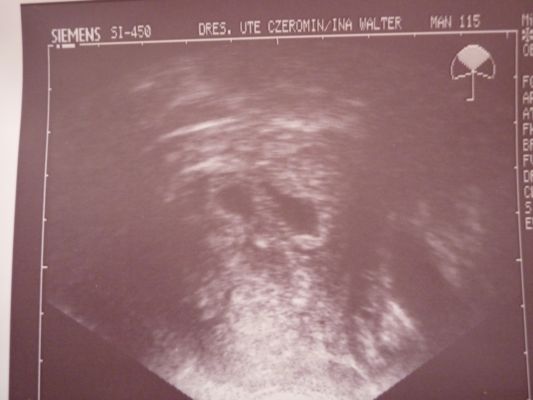

Also der US war soweit ganz gut!Leider gab es für uns noch keinen Herzschlag aber laut Ärztin alles soweit gut entwickelt!Fruchthöhle ist 15 mm mit einem Dottersack.Und dann die Überraschung, man konnte noch eine Fruchthöhle sehen die jedoch deutlich kleiner ist (9mm) und noch leer.

Laut Ärztin ist die große Fruchthöhle gut entwickelt und ich soll nächste Woche Freitag wieder kommen und mir keine Sorgen machen weil wir noch kein Herzchen gesehen haben!Bei der kleinen Fruchthöhle müssen wir erstmal schauen wie sie sich weiter entwickelt!

@Leo: Ach einfach wunderschön so ein US-Bild, oder? Wie hast Du denn das hier reingestellt? Also eingescannt oder wie geht das?

Ach wegen dem Bild:

Wenn du bei Antworten etwas nach unten gehst dann siehst du da die Option "Attachment hinzufügen" da gehst du auf "Durchsuchen" und läds das Bild hoch,zuerst aber einscannen

(ich habs abfotografiert) aber achte darauf das die Datei nicht zu groß ist.Dann muss du noch auf "Attachment hinzufügen" klicken und dann auf "Antworten".Meistens will das Programm noch das du was dazu schreibst im Antwort-Fenster.Müsste aber klappen, habs auch so gemacht!

erstmal liebe @LEO-SYLVIA: Ich freue mich sehr für die schöne Fruchthöhle(n) und sei nicht traurig, das Herzchen bzw. die Herzchen schlagen ganz bestimmt schon nächste Woche. Aber kann Dich gut verstehen, es ist sicherlich erstmal entäuschend gewesen. Dei US-Bild sieht schön aus (willa auch!) und hier im Ordner ist wirklich eine Zwillingswelle (bei mir sicherlich nicht, kommt gleich). Ich denke, Justin freut sich über zwei Spielkameraden!!!!